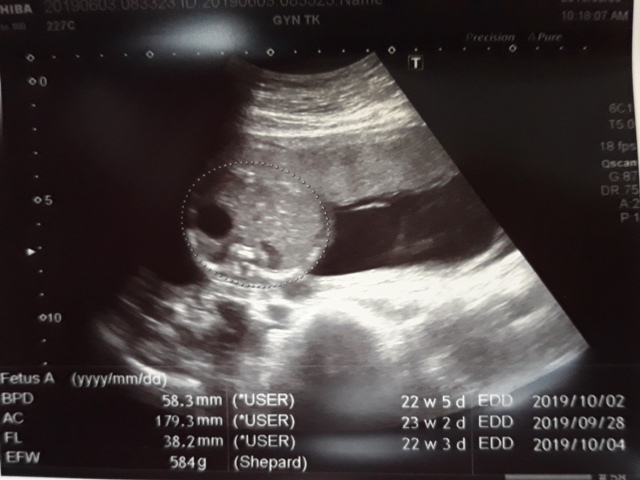

早上十點左右,和小純至澄清醫院做產檢,今日要做的是『妊娠糖尿病』的檢查(一般來說,妊娠糖尿病是24週 - 28週檢查,不過小純今天是第23週又3天,還沒到24週),首先我們先到抽血室去,護理師拿了五瓶裝的美達妍注射液讓小純喝,喝完之後一個小時以後再進行抽血。來之前小純有跟我說過,驗妊娠糖尿病要喝很甜的 糖水,但她今天喝了,感覺還好,不會很甜。

近五次產檢資料統計

| 日期/項目 | BPD | AC | FL | EFW | 心跳 |

| 2019年03月04日 | 無資料 | 無資料 | 無資料 | 無資料 | 無資料 |

| 2019年04月01日 | 28.9mm | 77.9mm | 14.2mm | 107g | 153 |

| 2019年04月29日 | 41.7mm(44%) | 125.7mm(61%) | 28.9mm(103%) | 241g(125%) | 150 |

| 2019年05月22日 | 53.4mm(28%) | 160.6mm(28%) | 34.6mm(20%) | 408g(69%) | 150 |

| 2019年06月03日 | 58.3mm(9%) | 179.6mm(12%) | 38.2mm(10%) | 584g(43%) | 157 |

| BPD:胎兒頭骨橫徑 AC:胎兒腹圍的長度 FL:胎兒大腿骨的長度 EFW:胎兒的體重 括弧內百分比為較上次產檢的成長比例 | |||||

今天關醫師也把4月22日所做的羊膜穿刺及羊水晶片的報告拿給我們,一切都正常。